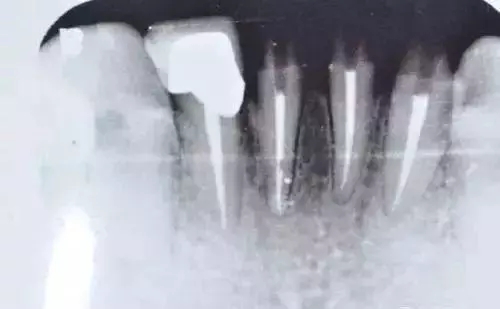

劉小姐的烤瓷牙在使用了六年之后,雖然仍能夠正常飲食,但卻一直斷斷續(xù)續(xù)出現(xiàn)牙痛的癥狀,靠吃著消炎藥來(lái)緩解疼痛。直到前不久,劉小姐發(fā)現(xiàn)左邊上排的烤瓷牙出現(xiàn)松動(dòng),于是才到醫(yī)院進(jìn)行檢查。經(jīng)過(guò)檢查發(fā)現(xiàn),她的牙冠內(nèi)存在的基牙都已經(jīng)全部發(fā)炎,并開(kāi)始腐爛,只能拔除剩余的腐爛基牙,做全口固定的種植牙。